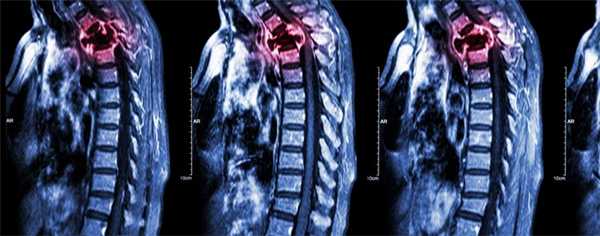

(Слева) На рентгенограмме в бо ковой проекции визуализируется мягкотканная опухоль, замещающая невральную дугу С2. Также определяется деструкция верхнего края боковых масс СЗ. Распространение деструктивных изменений от одной кости к другой нетипично для метастатического поражения.

(Справа) На сагиттальной MPT (Т1 ВИ) у этого же пациента визуализируется крупный очаг в невральной дуге С2. Костный мозг зубовидного отростка замещен опухолью. На рентгенограммах поражение зубовидного отростка выявлено не было - чувствительность МРТ в обнаружении метастазов выше.

(Слева) На рентгенограмме в боковой проекции у пациентки с распространенным бласти -ческим метастатическим поражением на фоне рака молочной железы определяется диффузный склероз шейных позвонков и основания черепа. Видны наложения от сережек.

(Справа) На сагиттальной MPT (Т1 ВИ) определяются множественные остеобластические метастазы с сигналом крайне низкой интенсивности, свидетельствующим о их бластическом характере. Типоинтенсивный сигнал должен сохраняться и во всех стальных последовательностях.